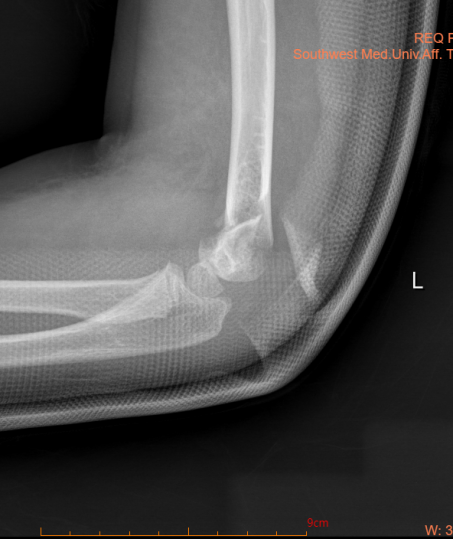

1.Ⅲ型肱骨髁上骨折,骨折断端已经完全移位,没有稳定性,几乎无骨膜,无皮质,骨折端几乎没有骨膜连接支撑,断端极度不稳定,保守治疗会导致骨折端畸形愈合,可能产生一系列后遗症及并发症,对儿童生长发育有比较大影响,因此需要手术治疗;

2.Ⅱ型肱骨髁上骨折,如果内侧端出现压缩或旋转移位,建议手术治疗,否则骨折愈合后容易出现肘关节内翻畸形,影响上肢外观及功能;

肱骨髁上骨折闭合复位经皮克氏针内固定术